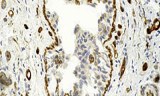

Les coupes tissulaires sont de fines tranches de tissu biologique préparées pour des examens microscopiques et des analyses moléculaires, fondamentales en histopathologie, biologie moléculaire et recherche biomédicale. Elles permettent la visualisation détaillée et la localisation de structures cellulaires, de l’ADN, de l’ARN et de marqueurs protéiques, facilitant l’étude des tissus sains et pathologiques.

- Localisation et identification de l’ARNm et des marqueurs protéiques dans des contextes tissulaires spécifiques.

- Détection de marqueurs tumoraux et de gènes spécifiques aux maladies à des fins diagnostiques et de recherche.

- Étude des profils d’expression génique et protéique dans les tissus normaux et pathologiques.